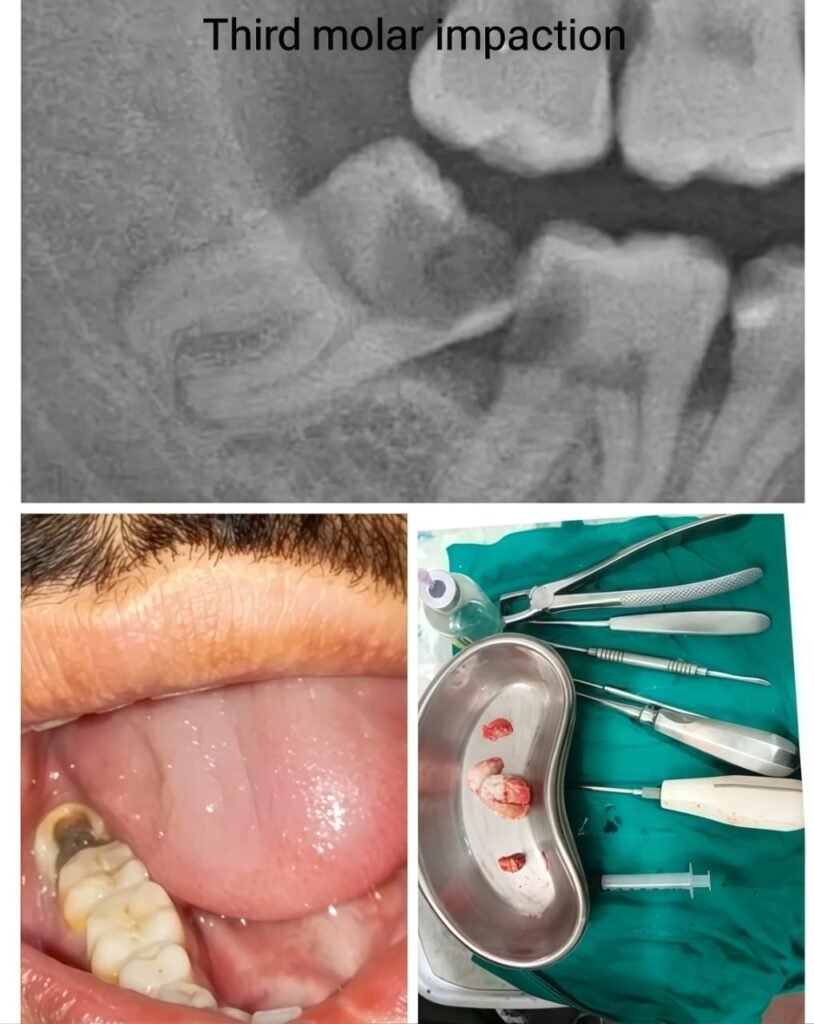

Before & After Case Studies

Our patients experience life-changing transformations. These cases demonstrate our commitment to exceptional results. Each success story represents our dedication to precision and aesthetic excellence.